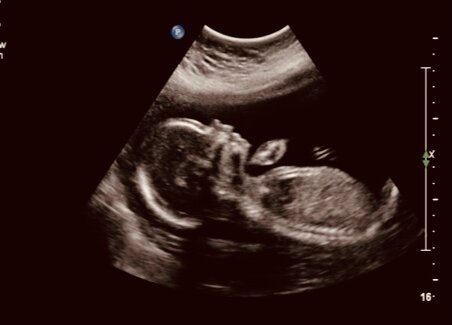

Ох уж это страшное слово «скрининг». Это обязательное обследование назначают к 12 неделям. К этому период ваш малыш прошел уже большой путь и уже визуально напоминает маленького человечка. Но в то же самое время он очень уязвим. Именно сейчас с большей вероятностью можно обнаружить различные пороки.

Скрининг первого триместра включает в себя УЗИ и биохимический анализ крови. На УЗИ врачи могут увидеть начальные признаки разных аномалий, а также определить размеры плода, точный срок беременности. Кстати этот срок не обязательно должен совпадать с тем сроком, что Вам поставил врач-гинеколог. Поскольку на УЗИ врач определяет на какой именно срок развит ребенок, а гинеколог отсчитывает срок от даты последних месячных. Разница может быть в 2 недели, не пугайтесь. В зависимости от того к какой стенке матки (передней или задней) прикреплен плод Вас могут попросить опорожнить мочевой пузырь, поскольку плода в некоторых случаях не видно.